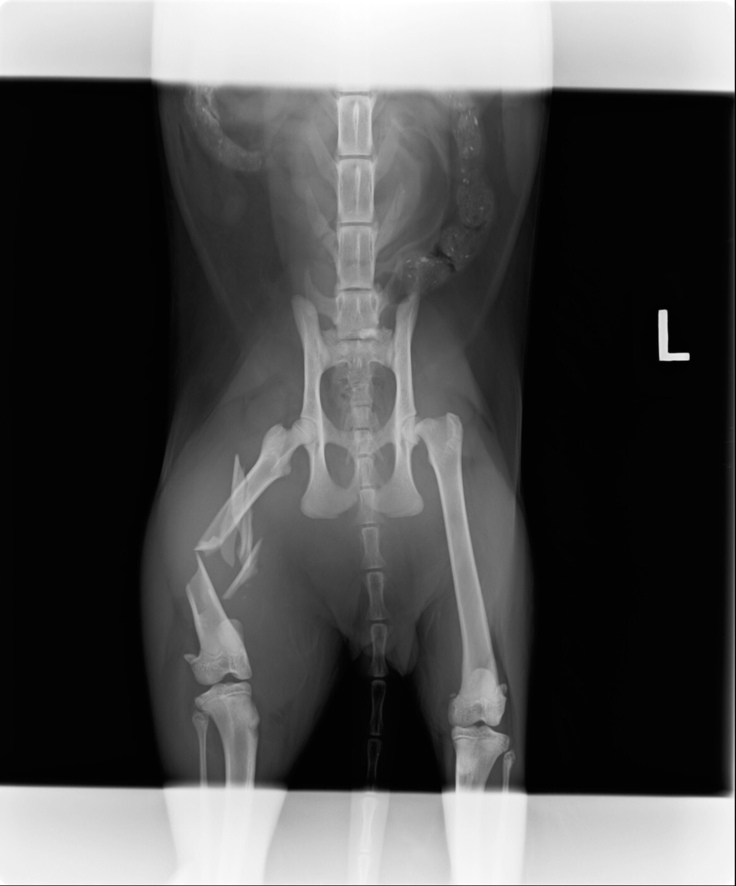

レントゲンでは右腿骨折、膀胱や尿道の損傷により血尿が出ているという状態で、獣医師から

手術結果は切開してみると、骨折が思いのほか酷く膝下まで達していたので、処置の施しようが無く右脚脱脚となってしまいました。

まだ、左脚股関節のピンが入っていて今後も通院の必要があります。

心配していた残った左足股関節のピンで留めていた部分が外れて再手術になりました。

ピンを抜き骨頭を切除する手術になります。

ここの部分です。以前のレントゲンです🙏

半球状の部分をカットしました。